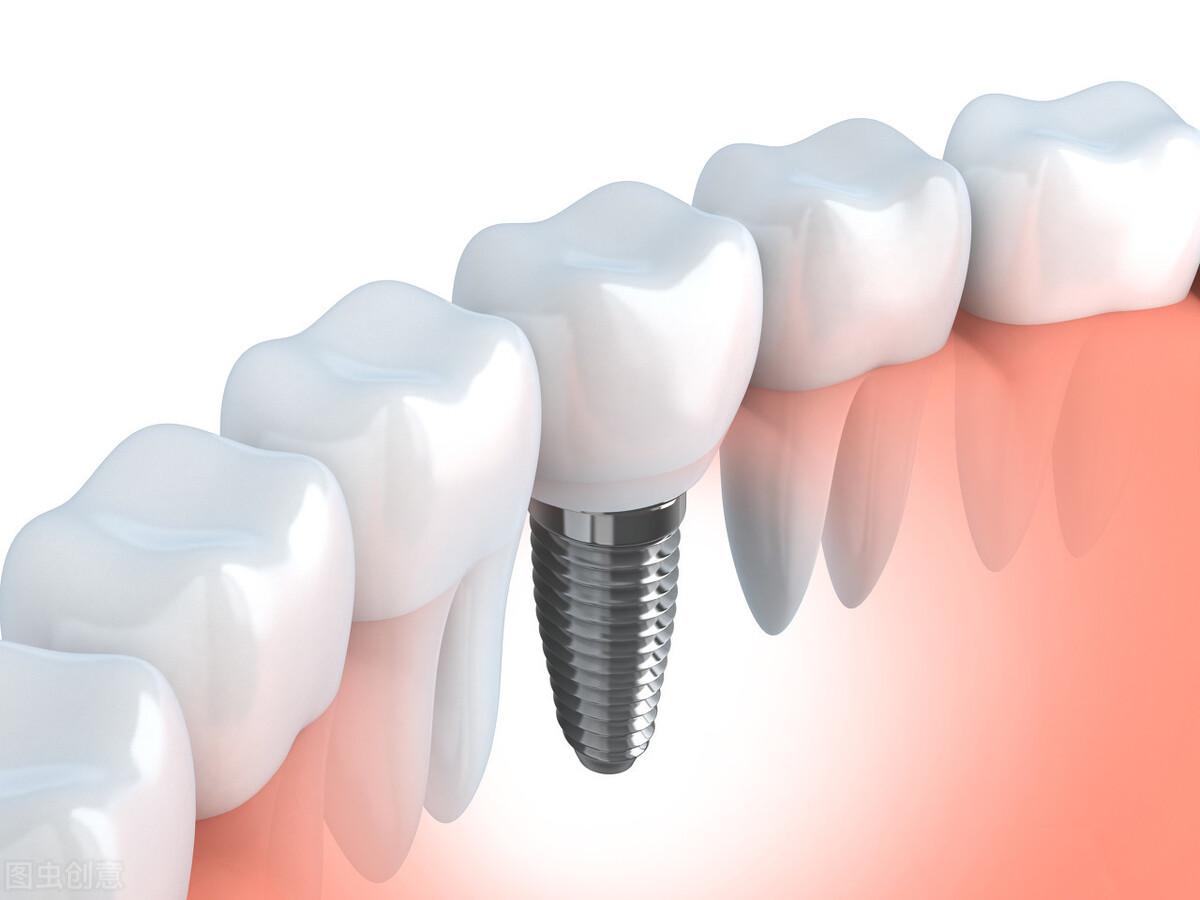

種植牙,全稱為人工種植牙,分成三個(gè)部分:種植體(人工牙根)、基臺(連接體)和牙冠(牙齒)。

種植體是一種高度精密的螺絲構(gòu)造,它外部的螺紋和微表面結(jié)構(gòu)與牙床骨接觸,引導(dǎo)牙床骨細(xì)胞生長到種植體表面,以達(dá)到種植體與牙床骨充分結(jié)合,增強(qiáng)其咀嚼力量及穩(wěn)定性能的目的。